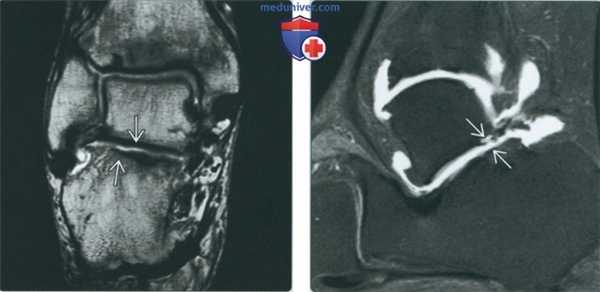

(Слева) МР-артрография в режиме Т1ВИ FS, аксиальный срез: визуализируется разрыв латеральной коллатеральной связки вследствие травматического приведения большого пальца. Отмечаются проксимальная ретракция волокон ЛКС и распространение контрастного препарата через дистально расположенный дефект. МКС не изменена.

(Справа) МР-артрография в режиме Т1ВИ FS, коронарный срез, этот же пациент: определяется дефект ЛКС. Мягкие ткани подошвы не изменены. (Слева) МР-артрография в режиме Т1ВИ FS, коронарный срез: определяется распространение контрастного препарата через дефект в проксимальном крае подошвенной связки 1-го плюснефалангового сустава вследствие избыточного тыльного сгибания большого пальца.

(Справа) МР-артрография в режиме PD FS, аксиальный срез, этот же пациент: определяется локальный разрыв подошвенной связки. Отмечается распространение жидкости в проксимальном направлении между медиальной и латеральной головками короткого сгибателя большого пальца. (Слева) Артрография 2-го плюснефалангового сустава, передне-задняя проекция: визуализируется распространение контрастного препарата через разрыв в подошвенной связке. Медиальнее и латеральнее разрыва контур подошвенной части сустава не изменен.